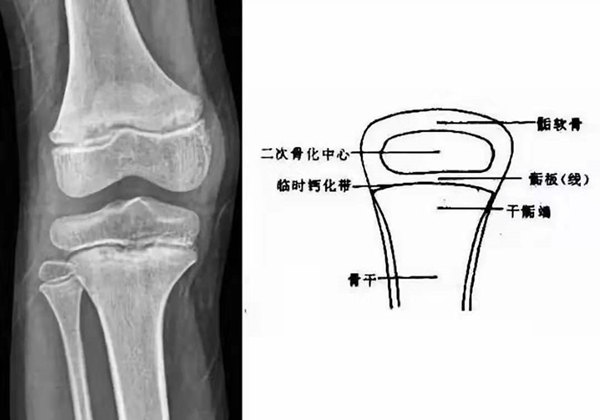

我們都知道,人體的高矮是由骨骼的生長發(fā)育決定的,特別是下肢長骨。長骨呈長管狀,在長骨的兩端有一種專管骨骼生長的骺軟骨,它與干骺端之間有一盤狀軟骨結(jié)構(gòu)稱為骺板(線),在幼兒的X光片上表現(xiàn)為一條較寬的透光帶。 (見下圖)

未成年時隨著年齡的增加骺軟骨端不斷骨化,骨骼就不斷增長。當骨骺線完全閉合時骨骼就停止生長,個子也就不再增長了。一般骨骺端完全閉合的年齡是18~20歲左右。